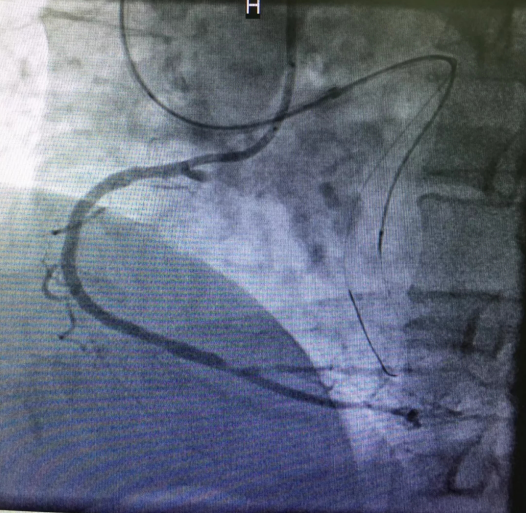

心内三完成啄木鸟 首例逆向开通冠脉CTO病变